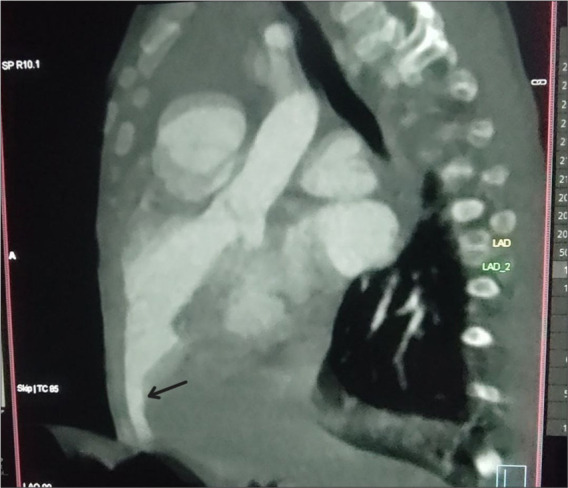

摘要左心室憩室(LVD)是一种罕见的先天性异常,其特征是左心室壁异常突出。它通常在儿童时期被发现,因为它通常与胸腹中线缺陷和其他先天性心脏异常有关。在这里,我们报告了一个10个月大的男婴,他患有下腹部血管病和脐膨出,需要手术治疗,术后断奶困难。我们讨论了独特的挑战,需要细致的规划和执行,以优化右心室功能和预防肺动脉高压在这类患者。

Left ventricular diverticulum (LVD) is a rare congenital anomaly characterized by an abnormal outpouching of the left ventricular wall. It is often identified during childhood, as it is commonly associated with midline thoracoabdominal defects and other congenital heart abnormalities. Here, we present a 10-month-old boy with a LVD and omphalocele posted for surgical management who had difficulty weaning in the post-operative period. We discuss the unique challenges that necessitate meticulous planning and execution to optimize right ventricular function and prevent pulmonary arterial hypertension in such patients.